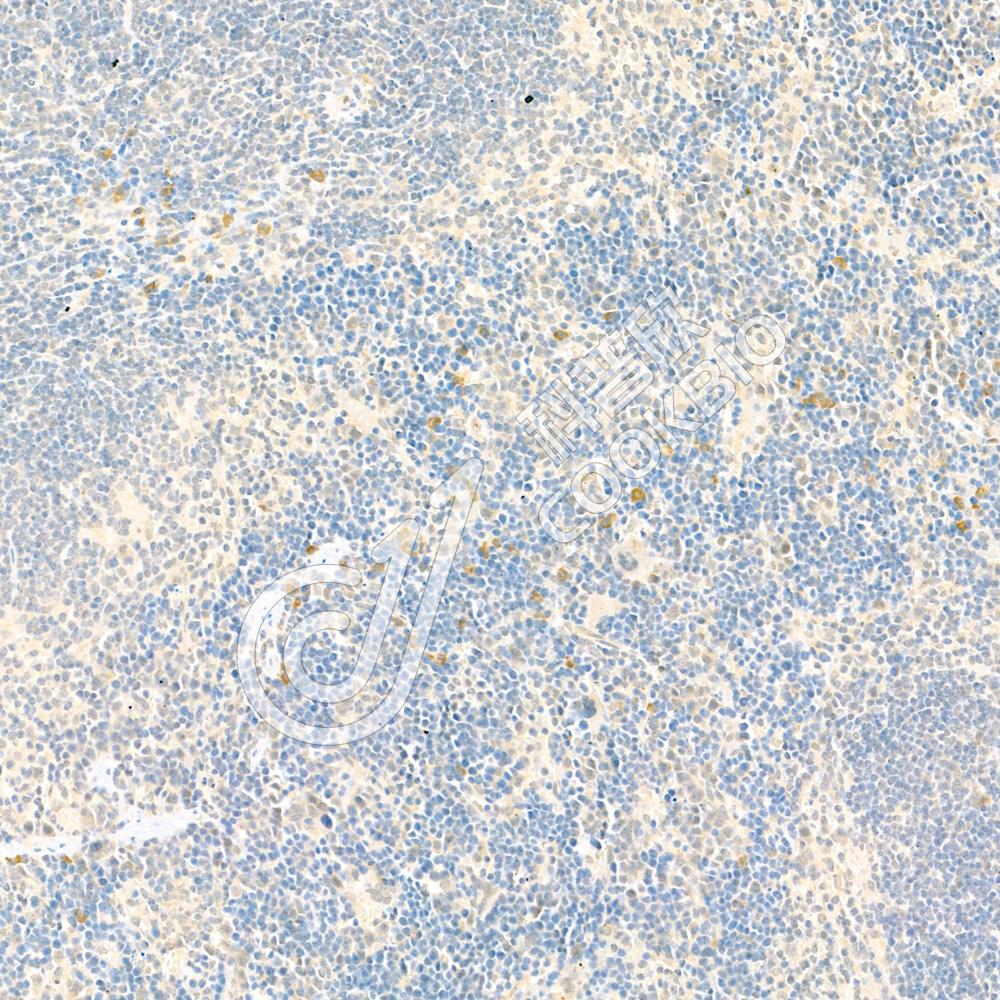

IHC检测Sodium Potassium ATPase蛋白(货号 K134200-1).

样品: 人结肠, 4%多聚甲醛 (货号KSG1101) 固定12-24小时.

抗原修复: 柠檬酸抗原修复液(干粉, pH 6.0) (KSG1201), 98℃, 20分钟.

—抗: 1: 800稀释, 4℃ 孵育过夜.

二抗: S-vision免疫组化多聚二抗(山羊抗兔),即用型 (货号KB3906), 室温孵育20分钟.